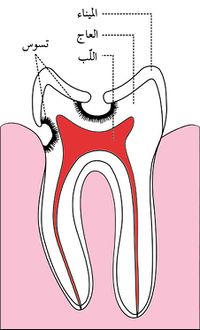

هو تخرب يصيب نسج السن الصلبة بدءاً من طبقة الميناء enamel ثم يصل إلى طبقة العاج محدثاً حفرة قد تزداد اتساعاً وعمقاً لتصل إلى اللب الذي يحتوي الأوعية الدموية والأعصاب.

حدوث التسوس وتطوره

تقوم الحموض الناتجة من عملية تخمر السكاكر بحل العناصر المعدنية والعضوية التي تدخل في تركيب ميناء السن فتبدو المنطقة بيضاء طبشورية وذات ملمس خشن. ولدى تزايد إنتاج الحموض وعدم تطبيق الفلوريد الموضعي على الأسنان الذي يقوم عادة بإيقاف تطور التسوس، يتهدم الميناء وتصل الإصابة إلى العاج مشكلة حفرة التسوس التي يمكن ملاحظتها سريرياً ويبدأ الإحساس بالألم لدى التعرض إلى مؤثرات خارجية من سخونة وبرودة أو الضغط أثناء المضغ. عند إهمال معالجة التسوس في هذه المرحلة يزداد التخرب وتصل الإصابة إلى لب السن الذي يصاب بالالتهاب وترافقه موجات حادة من الألم وخاصة في أثناء الليل. إن عدم تطبيق المعالجة الملائمة في هذه المرحلة يؤدي إلى تموت اللب وإصابته بالتعفن وتتكون الخراجات الحادة والمزمنة والآفات الذروية التي تنتهي بقلع السن المصابة.